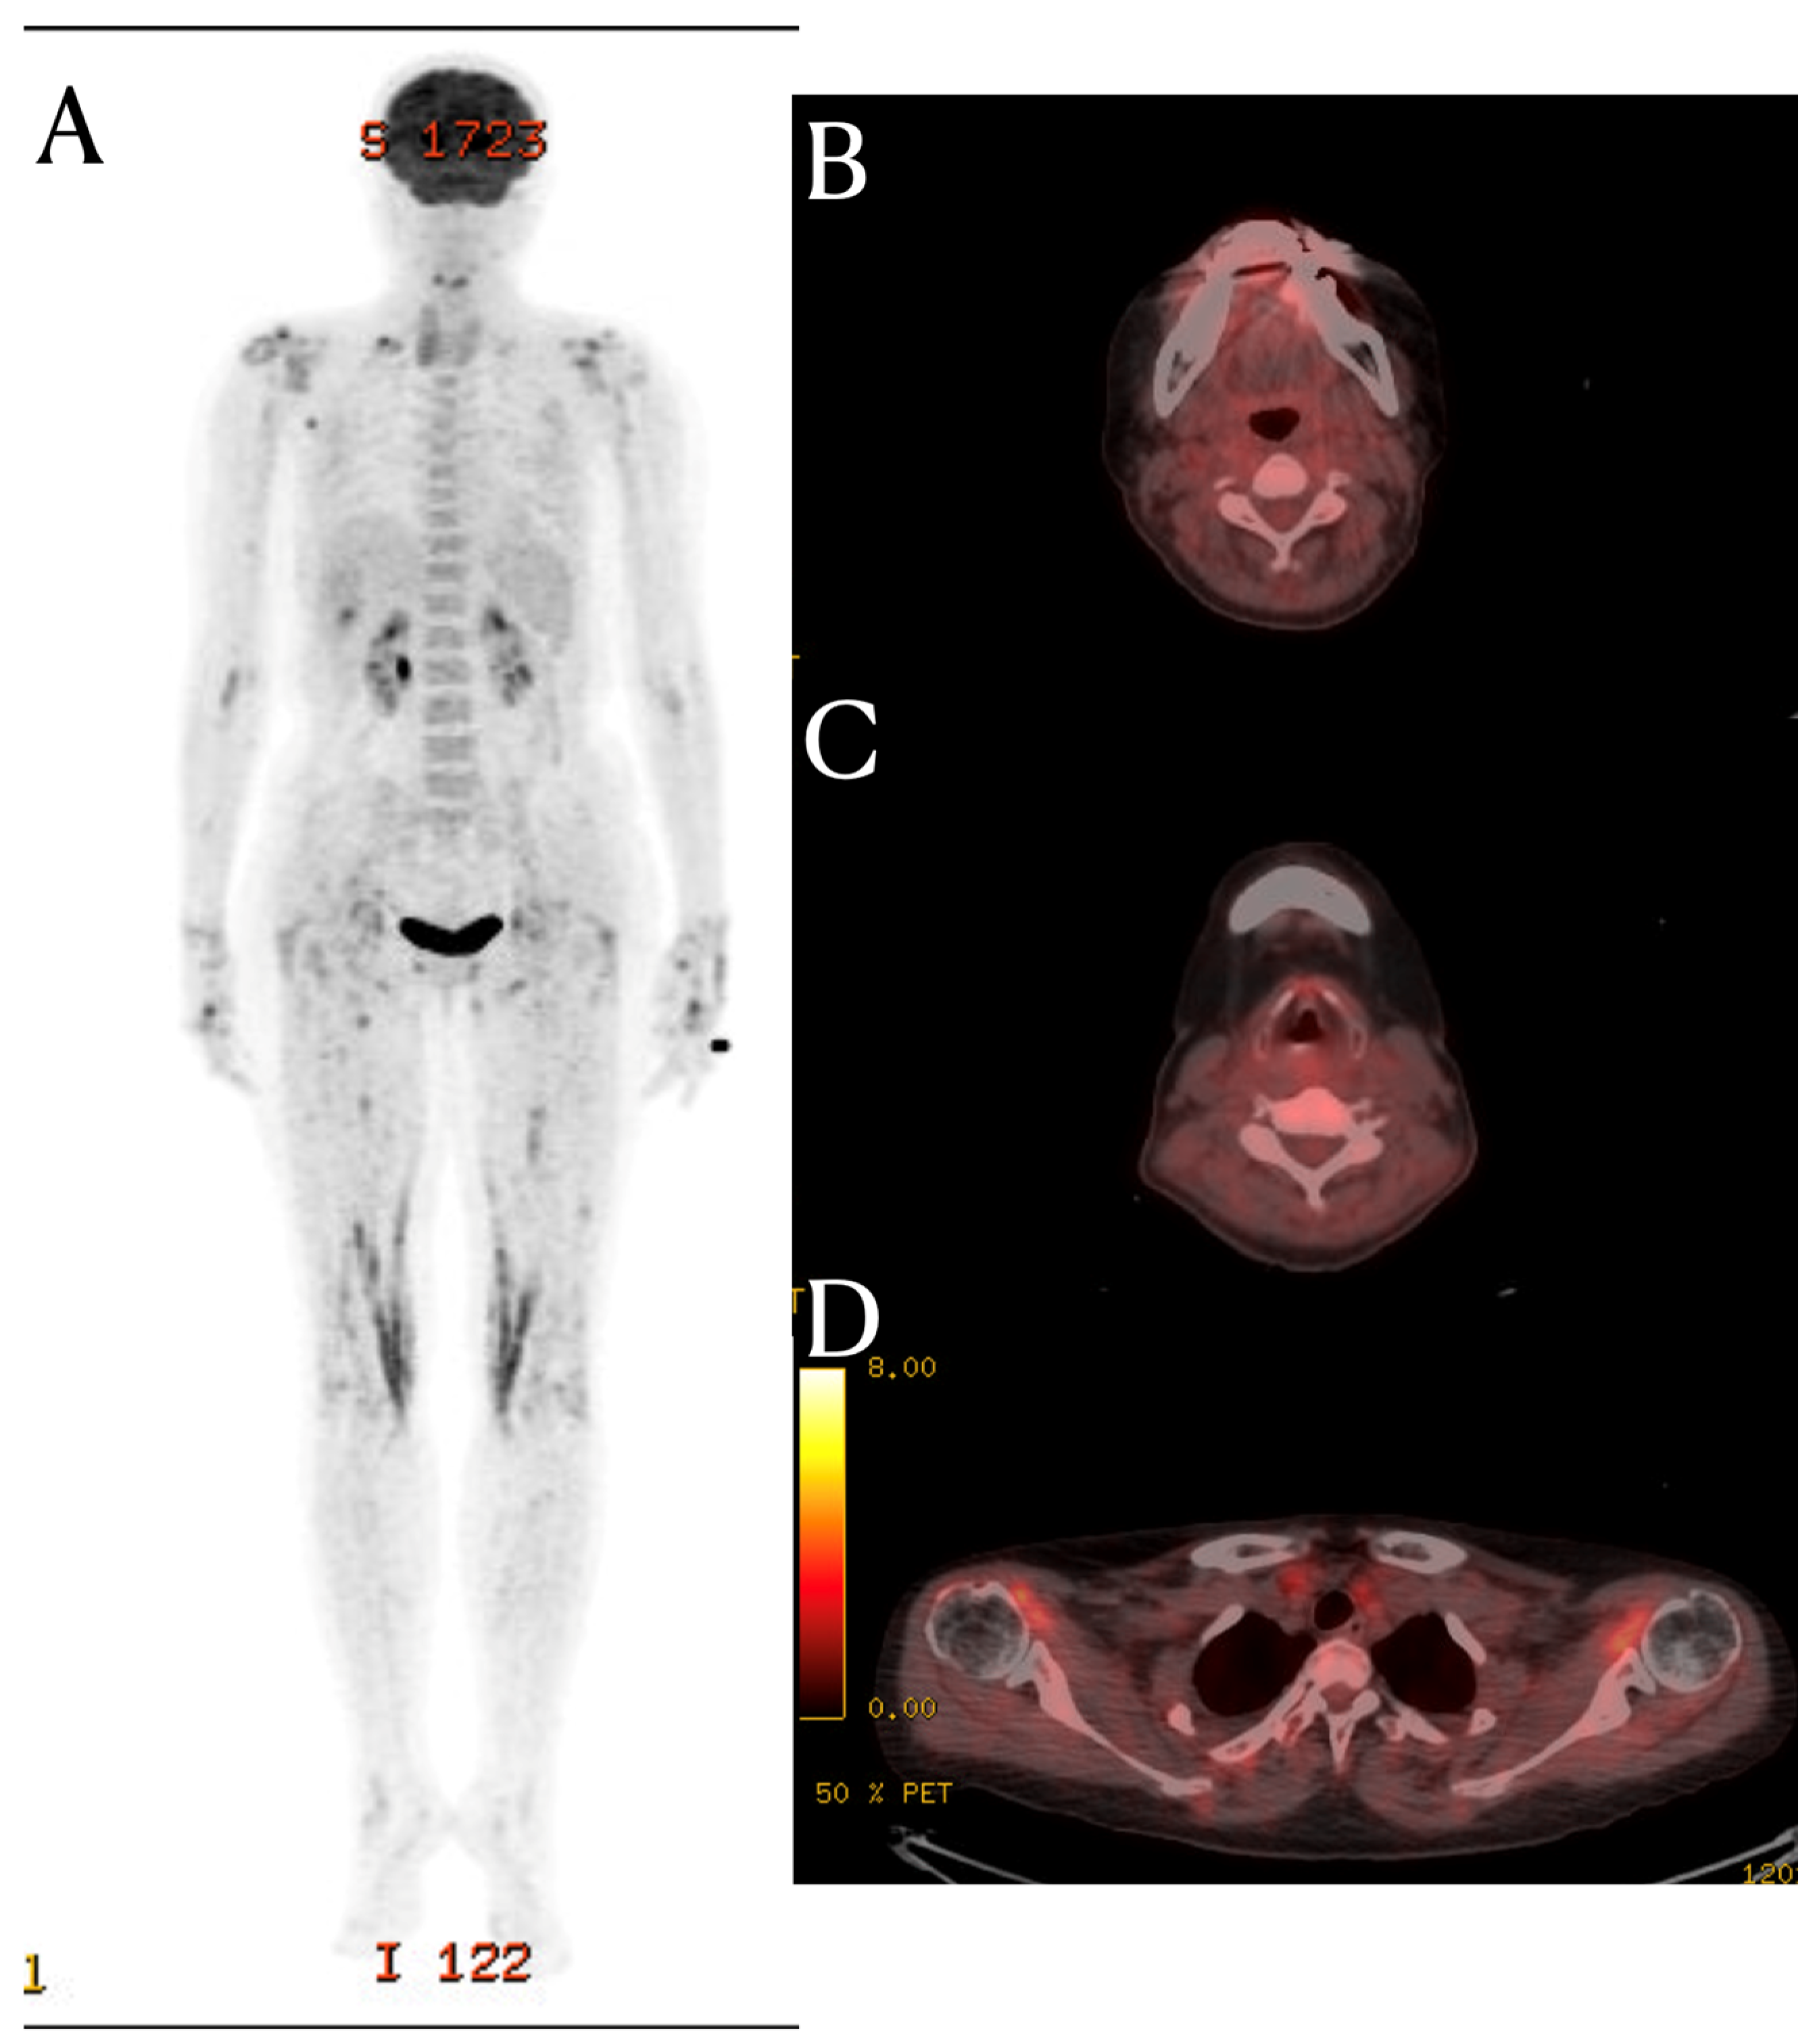

Although the PET-CT scan in this patient showed no evidence of FDG uptake in the prevertebral area and posterior neck fascia, it did reveal FDG uptake around multiple joints. (Figure 2) This suggests that this patient had systemic inflammation, which provides a possible explanation for the MRI signal changes. The fascia is a large complex of connective tissue found throughout the body. It contains nociceptors, meaning that inflammatory processes can lead to localized pain [6]. Additionally, many nerves traverse through the fascia to reach their respective locations; so, inflammation-induced changes in the extracellular matrix (ECM) can increase fascial stiffness [7]. These alterations can influence fascial nociception and stimulate nerves through stiffness, potentially causing musculoskeletal pains. So, hydrodilation procedures are performed to release peripheral nerve compression caused by stiff fascia [8]. The deep cervical fascia, palmar fascia, iliotibial band, and thoracolumbar fascia are known fasciae considered as potential causes of musculoskeletal pain [9]. While research on neck fascia is limited compared to other areas, previous study have shown increased fascia thickness in the SCM (sternocleidomastoid) and middle scalene muscles in patients with chronic neck pain [10]. Additionally, fascial manipulation reduced fascia thickness and pain.

Figure 2.

FDG PET-CT finding. Bilateral shoulder shows uneven FDG uptake (D). Both wrists, hips, and knees show increased FDG uptake (A). However, in the FDG PET-CT images of the C3 (B) and C5 spinal level (C), there is no hot uptake in the prevertebral soft tissue and posterior neck fascia areas, where signal changes were seen in the MRI.